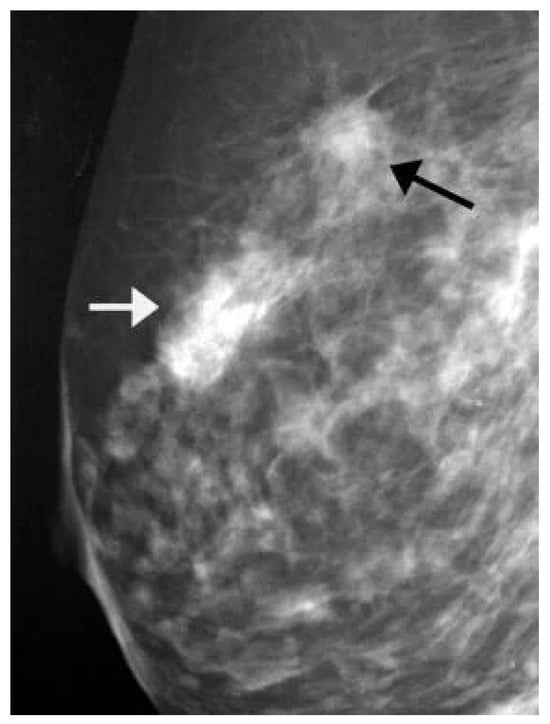

8.1. Mammogram Image-Based Breast Cancer Detection

8.1.1. Model Performance on Mammogram Image: Pros, Cons, and Future Directions